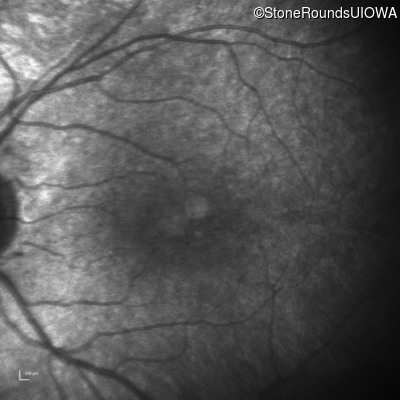

Infrared Fundus Photograph - Left - 20/32

Exemplar